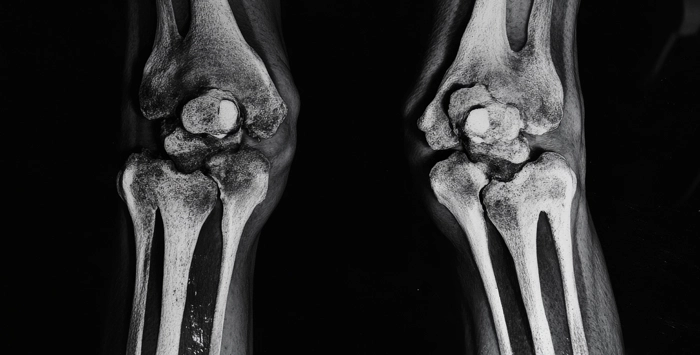

Η μέτρηση οστικής πυκνότητας, γνωστή και ως οστική πυκνομετρία ή DEXA (Dual-Energy X-ray Absorptionmetry), είναι μία διαγνωστική εξέταση που αξιολογεί την πυκνότητα των οστών και μας ενημερώνει για την ποσότητα τις οστικής μάζας.

Η εξέταση: Κατά την εξέταση θα ξαπλώσετε στην εξεταστική κλίνη και ο ανιχνευτής θα σαρώσει την περιοχή της σπονδυλικής στήλης και του ισχίου, για να μετρήσει την οστική πυκνότητα.